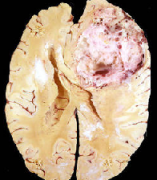

胶质母细胞瘤 是一种高度恶性的脑肿瘤,起源于神经系统中的支持细胞--星形胶质细胞。正常情况下,星形胶质细胞负责多种角色,包括为神经元提供营养...

胶质母细胞瘤生长速度很快,70%-80%患者病程在3-6个月,病程超过1年的患者仅10%,病程较长者可能由恶性程度低的星形细胞瘤演变而来...

胶质母细胞瘤(glioblastoma multiforme,GBM)是较常见的颅内原发性恶性肿瘤,占原发性脑肿瘤的80%,多见于老年人,其中65岁以上的人群占50%。胶质母细胞瘤是国际卫...